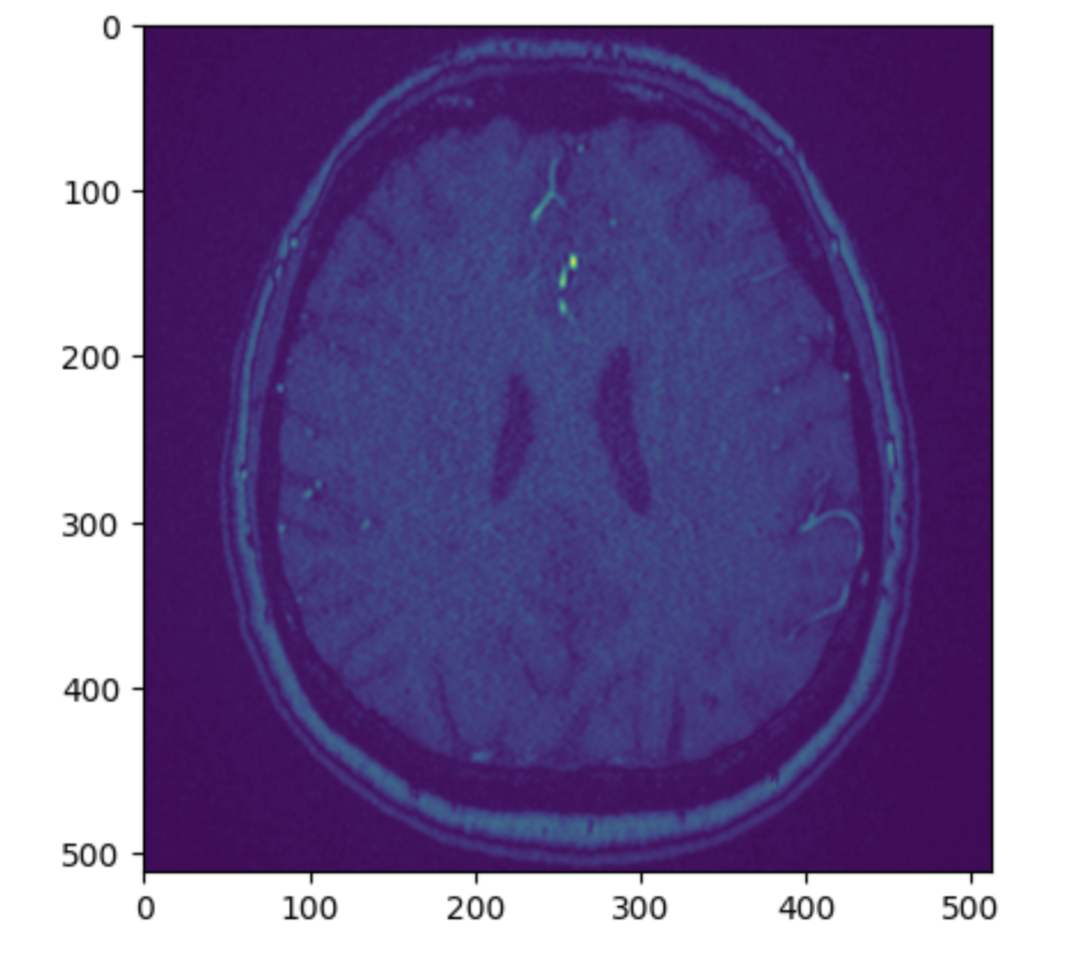

赛题类型:3D 计算机视觉

赛题任务:检测是否存在颅内动脉瘤,并精确定位其位置。

构建一个机器学习模型,利用多模态医学影像数据,检测是否存在颅内动脉瘤,并精确定位其位置。

精确定位:如果存在动脉瘤,需要预测它位于以下哪个(或哪些)具体的血管解剖部位。

包含了数千个由专家精心整理的脑部医学影像序列,这些影像来自多种不同的成像模式。每个序列都已被标注,指示在十三个可能的血管位置之一是否存在动脉瘤。